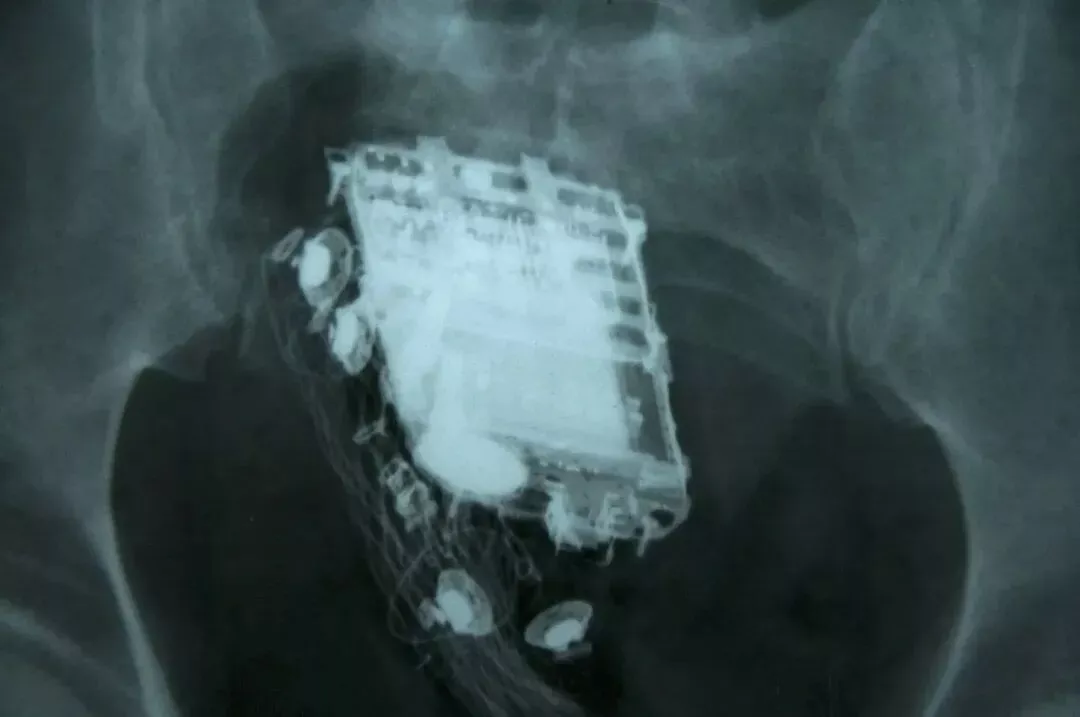

(电路板?)